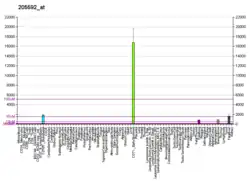

Band 3 anion transport protein, also known as anion exchanger 1 (AE1) or band 3 or solute carrier family 4 member 1 (SLC4A1), is a protein that is encoded by the SLC4A1 gene in humans.

The erythrocyte and kidney forms are different isoforms of the same protein.[6]

The erythrocyte isoform of AE1, known as eAE1, is composed of 911 amino acids. eAE1 is an important structural component of the erythrocyte cell membrane, making up to 25% of the cell membrane surface. Each red cell contains approximately one million copies of eAE1.